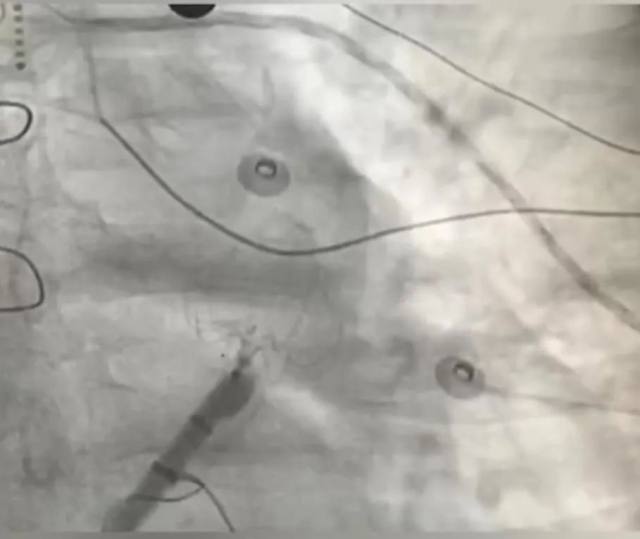

左心耳封堵器的植入

术中 ICE 指导左心耳封堵器植入